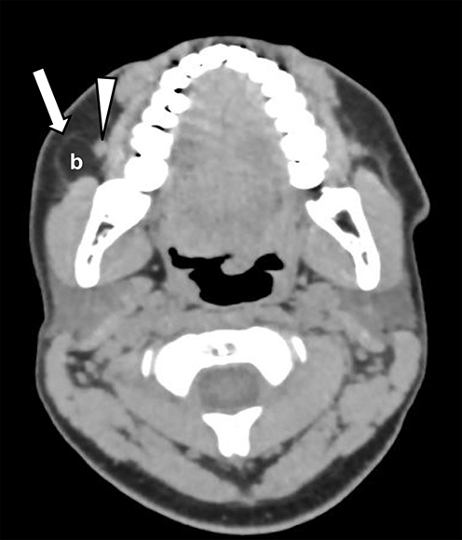

Corte axial de TC sin contraste endovenoso. Niño de 12 años de edad, que consultó por cefalea persistente, refiriendo también que se palpa un bulto en la hemicara derecha. Nótese la existencia de grasa prominente en topografía de la bola de Bichat (b), que desplaza la fascia cervical superficial (flecha) y el conducto de Stenon (cabeza de flecha) derechos. Ese hallazgo corresponde a un lipoma de la bola de Bichat. El conducto de Stenon se observa en forma parcial.